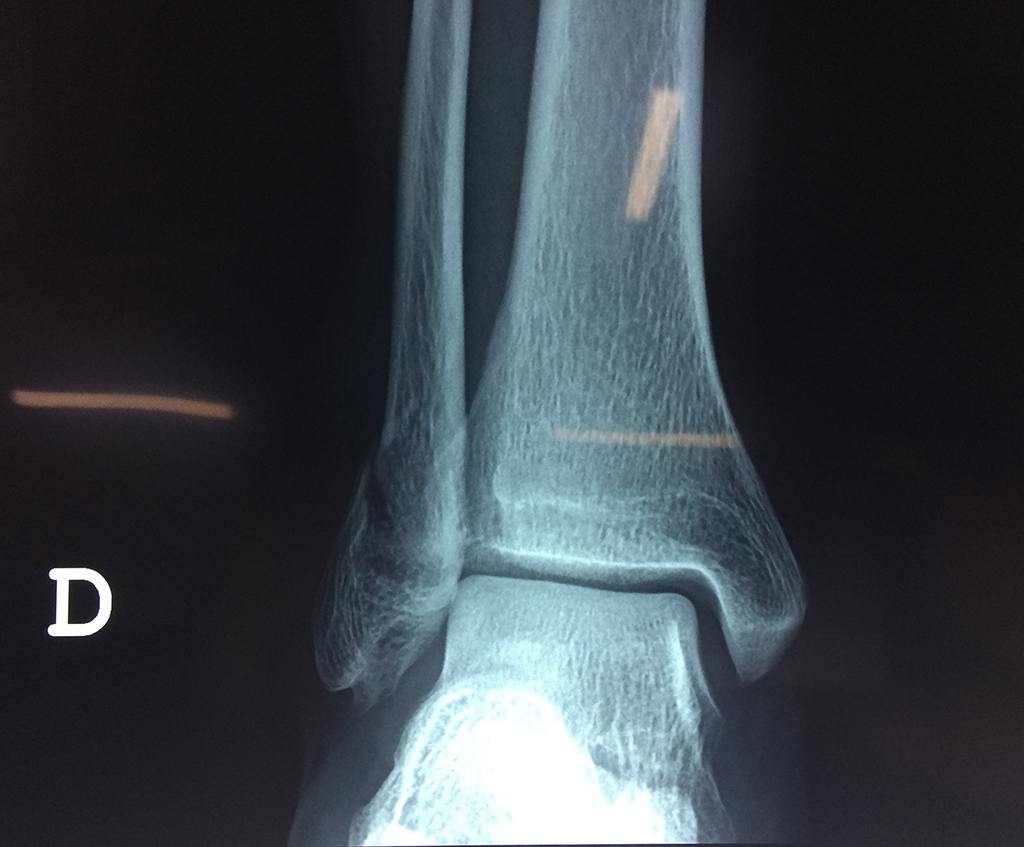

Una fractura de tobillo es la rotura de uno o más de los huesos del tobillo. Estas fracturas pueden ser:

- Parciales (el hueso está sólo parcialmente fisurado, no del todo).

- Completas (el hueso está perforado y está en 2 partes).

- Producirse en uno o ambos lados del tobillo.

- Los extremos de los huesos están desalineados entre sí (desplazados).

- La fractura se extiende hasta la articulación del tobillo (fractura intra-articular).